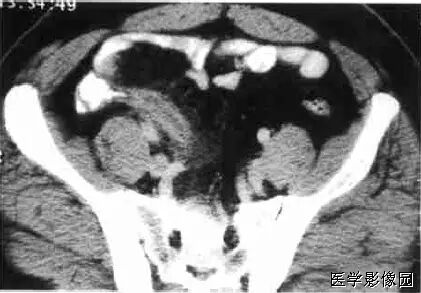

7、腹茧症

全部或部分小肠被一层致密、灰白色的纤维膜所包裹,形似“蚕茧”,故称为腹茧症,又称为特发性硬化性腹膜炎、小肠禁锢症、小肠纤维膜包裹症等。多见于青春期女性。腹部CT十二指肠空肠交界处扭曲,肠系膜增厚伴上消化道扩张,提示不全性肠梗阻。X线可发现全部或部分小肠聚拢于某一部分,位置固定。CT检查有更助于腹茧症的术前诊断。CT能显示梗阻程度及包块内肠管的情况,还能显示包裹在肠管周围的纤维包膜。一旦观察到包膜便可诊断腹茧症。典型的CT表现为扩张的小肠肠袢固定在腹部的某一部位,并被增厚的包膜所包裹或分割。增强扫描示包膜强化明显,部分病例可见腹腔积液及肠管间积液。

鉴别诊断:需要与腹膜包裹症鉴别,后者

不全肠梗阻